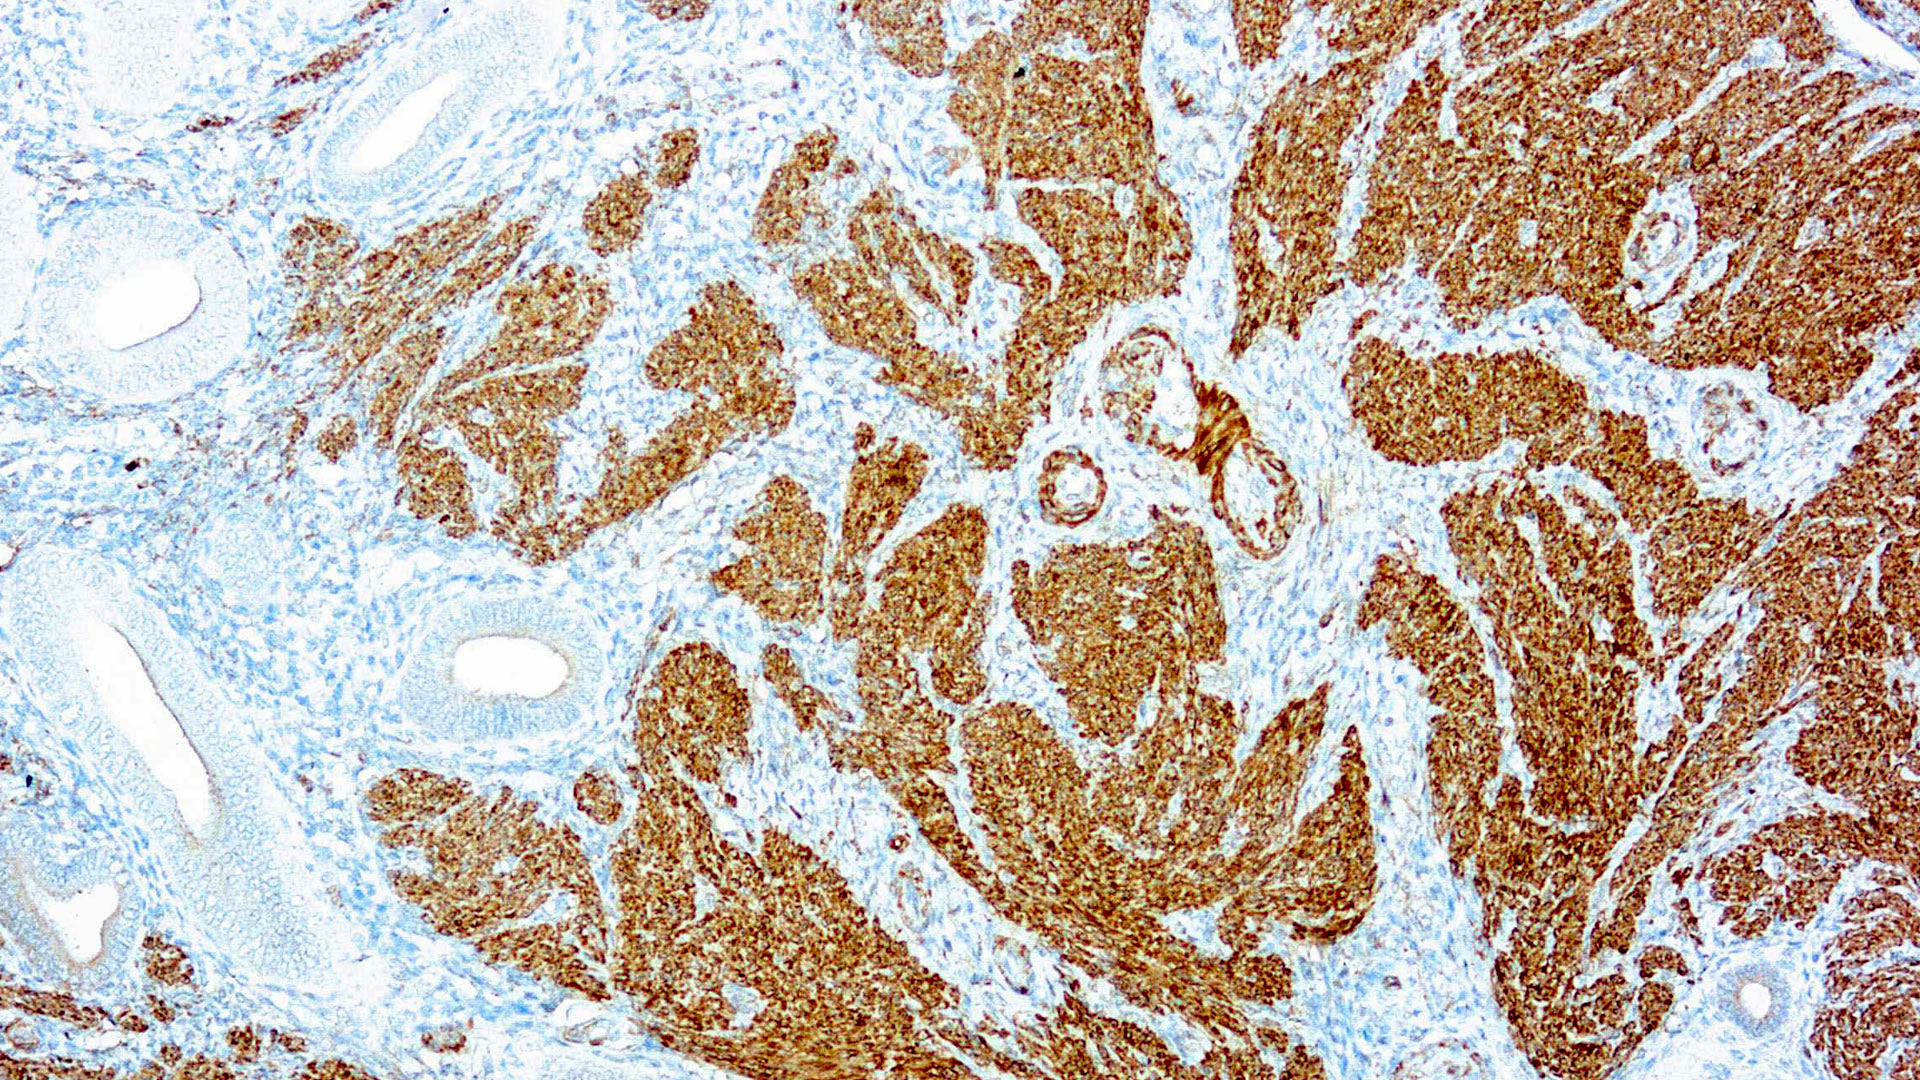

Calponin-1

Multiple isoelectric variants of calponin have been identified but only two molecular weight isoforms exist (34kDa and 29kDa). Expression of the 29kDa form, I-calponin, is primarily restricted to muscle of the urogenital tract, whereas the higher molecular weight variant has been demonstrated in vascular and visceral smooth muscle. Calponin is a calmodulin, F-actin and tropomyosin binding protein, which is thought to be involved in the regulation of smooth muscle contraction. Calponin expression is restricted to smooth muscle cells and has been shown to be a marker of the differentiated (contractile) phenotype of developing smooth muscle.

| Positive Control Tissue | Uterus |